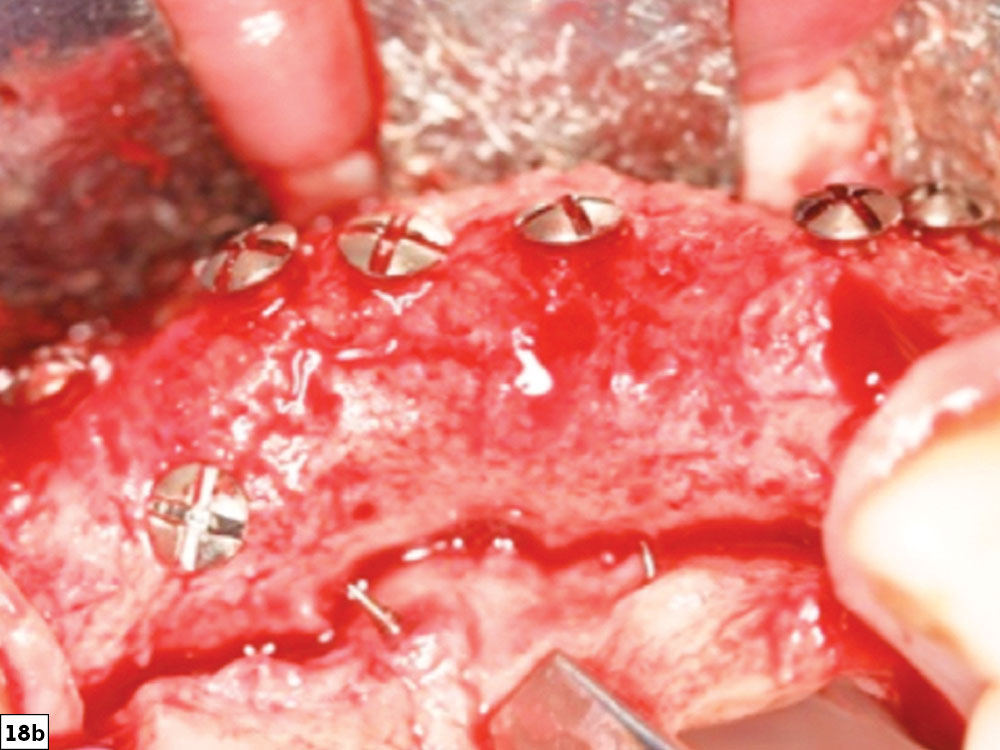

Straight/convex-type bone defect

Bone growth post-healing image

Figures 18a, 18b: Straight/convex-type bone defect (18a), and final post-healing image revealing bone growth in height and width ideal for future implant placement (18b).